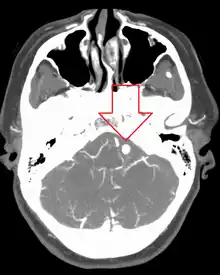

Ruptured 7mm left vertebral artery aneurysm resulting in a subarachnoid hemorrhage as seen on a CT scan with contrast

Diagnosis of a ruptured cerebral aneurysm is commonly made by finding signs of subarachnoid hemorrhage on a computed tomography (CT) scan. If the CT scan is negative but a ruptured aneurysm is still suspected based on clinical findings, a lumbar puncture can be performed to detect blood in the cerebrospinal fluid. Computed tomography angiography (CTA) is an alternative to traditional angiography and can be performed without the need for arterial catheterization. This test combines a regular CT scan with a contrast dye injected into a vein. Once the dye is injected into a vein, it travels to the cerebral arteries, and images are created using a CT scan. These images show exactly how blood flows into the brain arteries.